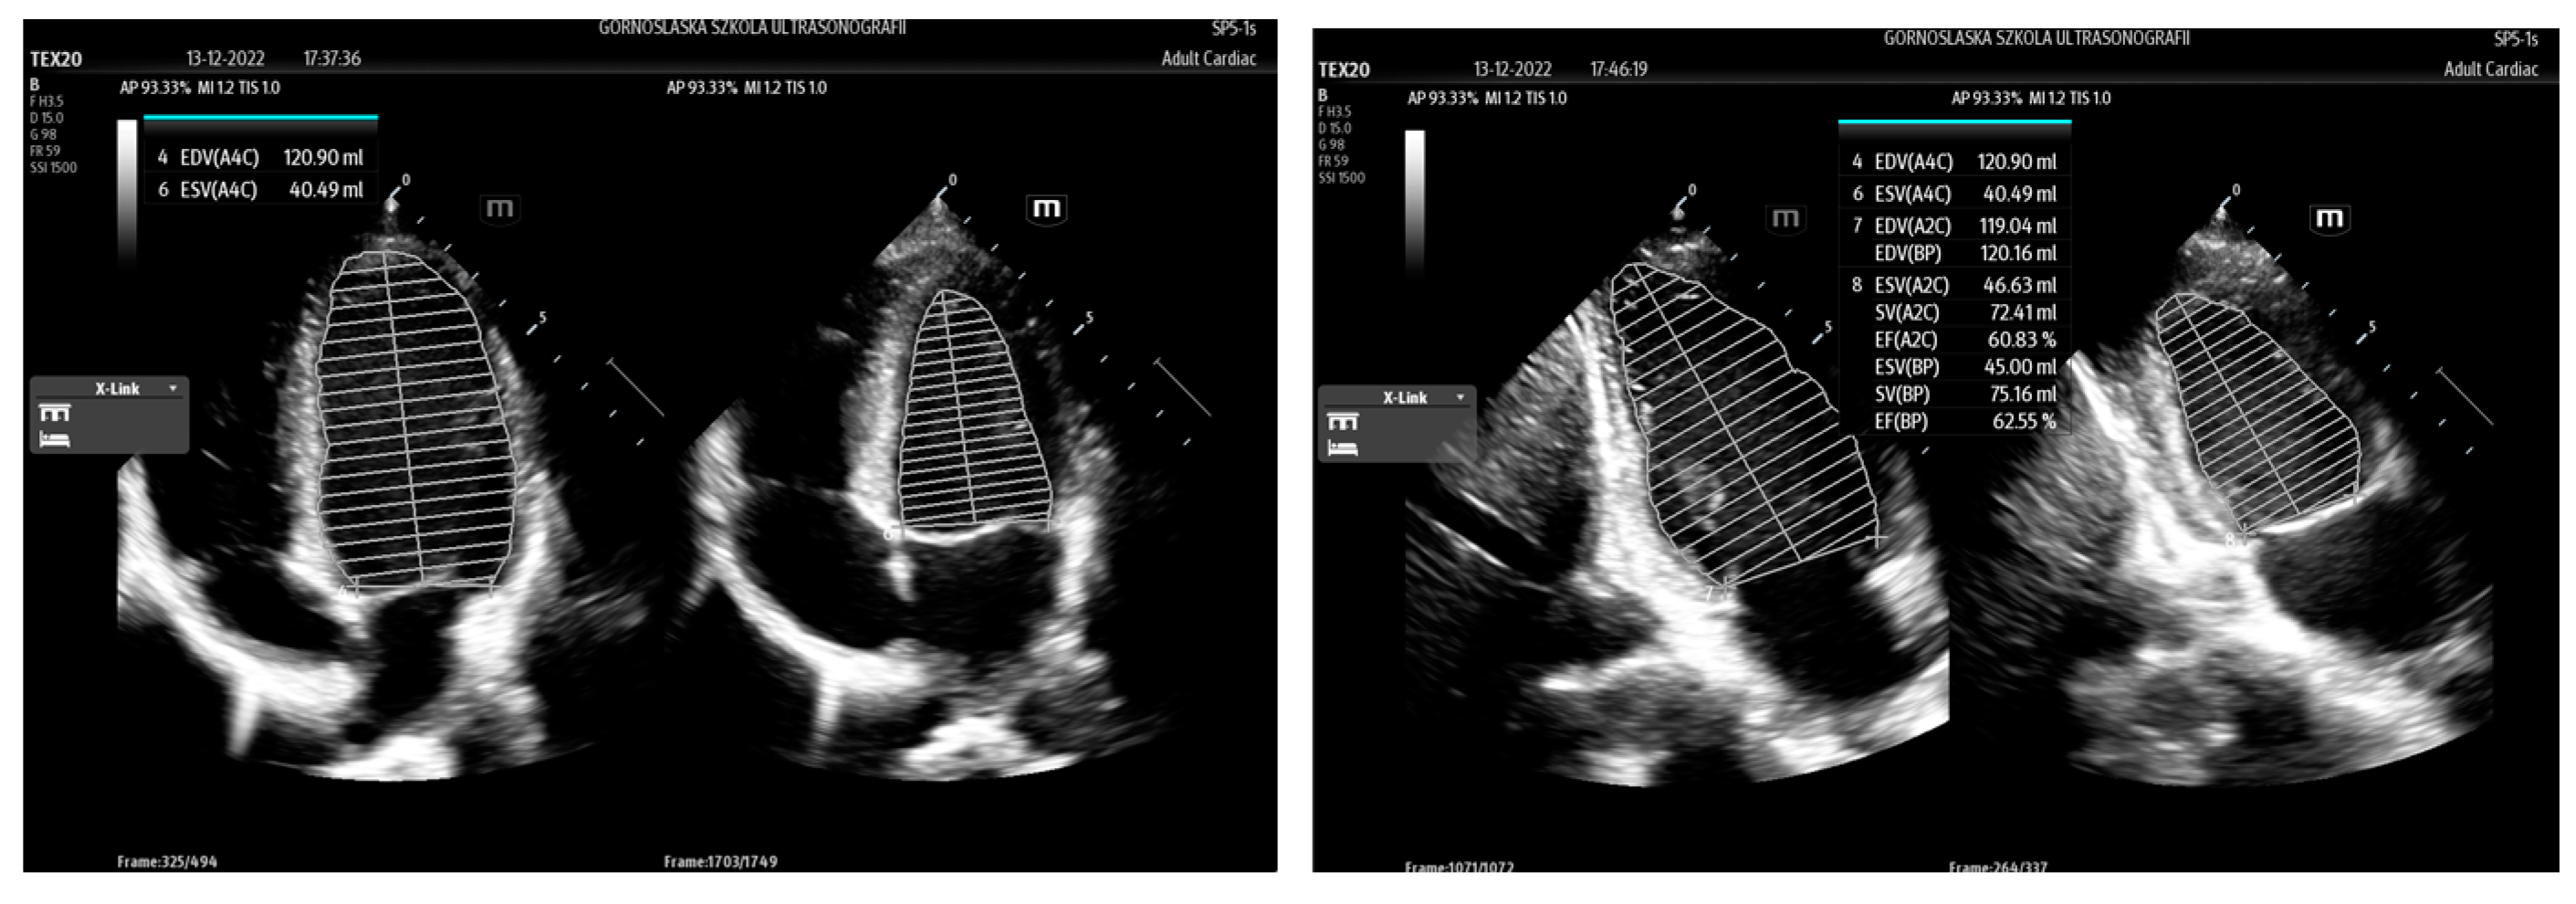

| AutoEF | Mindray | calculation of ejection fraction (EF) | Ultrasonographic assessment of cardiac function |

| LvivoEF | Philips | ||